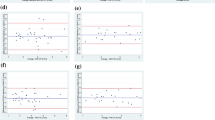

Pearson correlation index demonstrated a reasonable correlation between PWD-CO and PAC-CO measurements (r = 0.78, p < 0.0001) (Fig. 3). To compare CO by both techniques, a Bland–Altman analysis was performed and showed a bias of 1.03 L/min (± 1.27 L/min) with 95% limits of agreement ranging from − 1.50 to 3.56 L/min (Fig. 4). Less difference was seen between both techniques in patients with reduced cardiac output. In those patients with CO < 6.5 L/min, a bias of 0.46 L/min (± 0.88 L/min) with 95% limits of agreement of − 1.29 to 2.22 L/min was found.

The bias, precision, level of agreement, percentage of error, coefficient of variation, and coefficient of error are listed in Table 3. The mean PE between PWD-CO and PAC-CO was 17%. In one patient, the mean PE was higher than 30%. In this case, cardiac rate was normal with a high stroke volume and we could not explain the reason for this outlier.

Similar to previously published studies, our bias analysis showed a systematic underestimation of CO by PDW compared to thermodilution by PAC [24]. This discrepancy was more notable in patients with high cardiac outputs (Fig. 4), probably related to the influence of high flow velocities and turbulent flow over the PWD signal, variability of the VTI angle [25], physiologic fluctuations in stroke volume, and size of the aortic valve orifice [26].